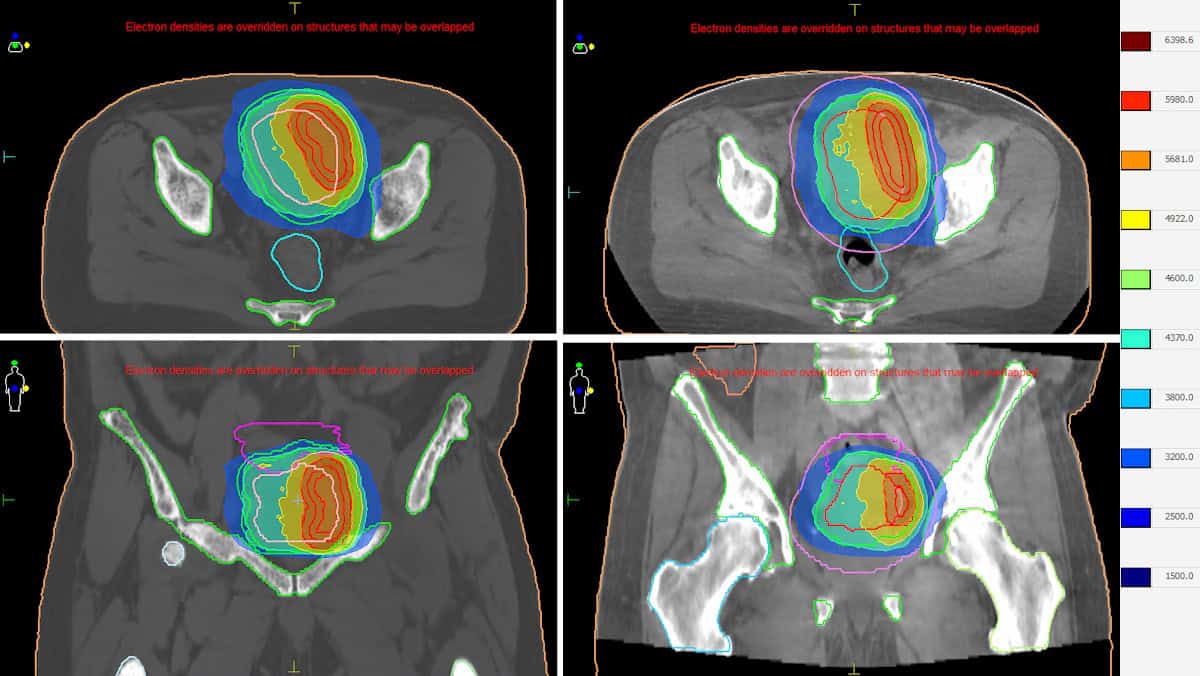

The ability to visualize and adapt to daily anatomy enables reduction of the planning target volume, increasing safety for nearby organs-at-risk (OARs). “It is highly beneficial for all treatments in the abdomen and pelvis,” says Lampe. “My patients with prostate cancer report hardly any side effects.”

The workflow begins with patient positioning and CBCT imaging, with Evo’s AI-enhanced Iris imaging significantly improving image quality, crucial when performing ART. The radiation therapist then matches the cone-beam and planning CTs and performs any necessary couch shift.

Simultaneously, Elekta ONE Online performs AI auto-contouring of OARs, which are reviewed by the physician, and the target volume is copied in. The physicist then simulates the dose distribution on the new contours, followed by a plan review. “Then you can decide whether to adapt or not,” says Lampe. “This is an outstanding feature.” The final stage is treatment delivery and online dosimetry.

Houweling says that ART delivery has taken 19 minutes on average. “We record the CBCT, perform image fusion and then the table is moved, that’s all standard,” she explains. “Then the adaptive part comes in: delineation on the CBCT and creating a new plan with Elekta ONE Planning as part of Elekta One Online.”

The plan adaptation, when selected to perform, takes roughly four minutes to create a clinical-grade volumetric-modulated arc therapy (VMAT) plan. With the soon to be installed next-generation optimizer, it is expected to take less than one minute to generate a VMAT plan.